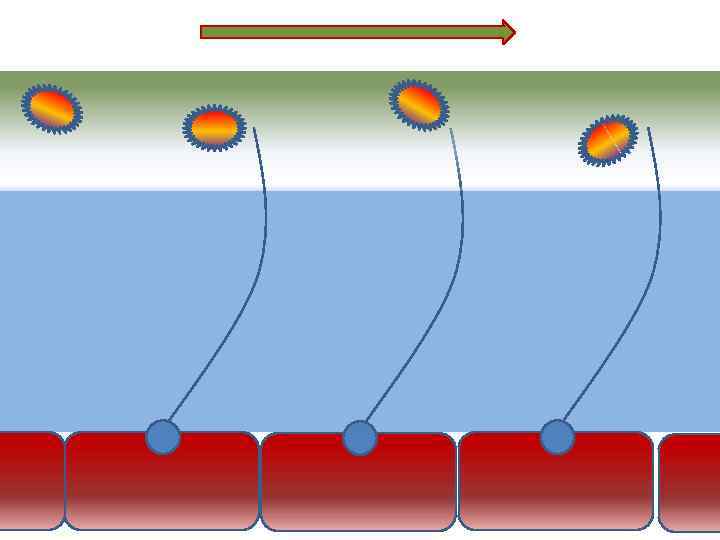

Механизм защиты легкого Слизь (зеленый цвет) нейтрализует и связывает патогенную флору(синий цвет) Слизь – это барьер между клетками и патогенной флорой Слизь – это транспортное средство

Механизм защиты легкого Слизь (зеленый цвет) нейтрализует и связывает патогенную флору(синий цвет) Слизь – это барьер между клетками и патогенной флорой Слизь – это транспортное средство